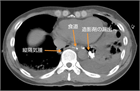

1. 食道破裂(esophageal rupture)、食道穿孔(esophageal perforation)や食道断裂(esophageal disruption)とは、食道壁に全層性に断裂(disruption)や損傷(trauma、injury)が生じた状態である。

1. 食道破裂(穿孔)は原因により、①特発性、②医原性、③外傷後性、④異物性、⑤化学的、⑥食道疾患によるものに分けられる。

1. 胸痛、呼吸困難、ショックなどの症状を呈する。